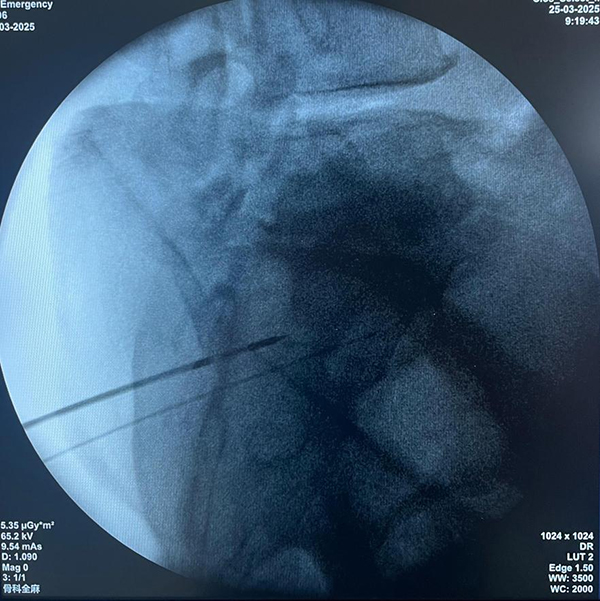

近年来,骨软组织肿瘤科紧密跟随医疗领域微创化、精准化的发展趋势,积极探索并开展多项前沿技术。在脊柱肿瘤治疗方面,科室熟练运用微创的经皮椎体成形术和微波消融技术,为患者提供创伤小、恢复快的治疗选择;对于复杂的脊柱肿瘤,也具备成熟的开放术式,确保治疗效果。在骨肿瘤保肢治疗上,科室不断突破技术瓶颈,通过精湛的手术技巧和先进的医疗设备,最大程度地保留患者肢体功能,提高生活质量。